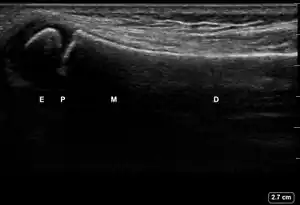

![]() Ultrasound lateral view of normal radius. E = epiphysis; P = physis; M = metaphysis; D = diaphysis. | |